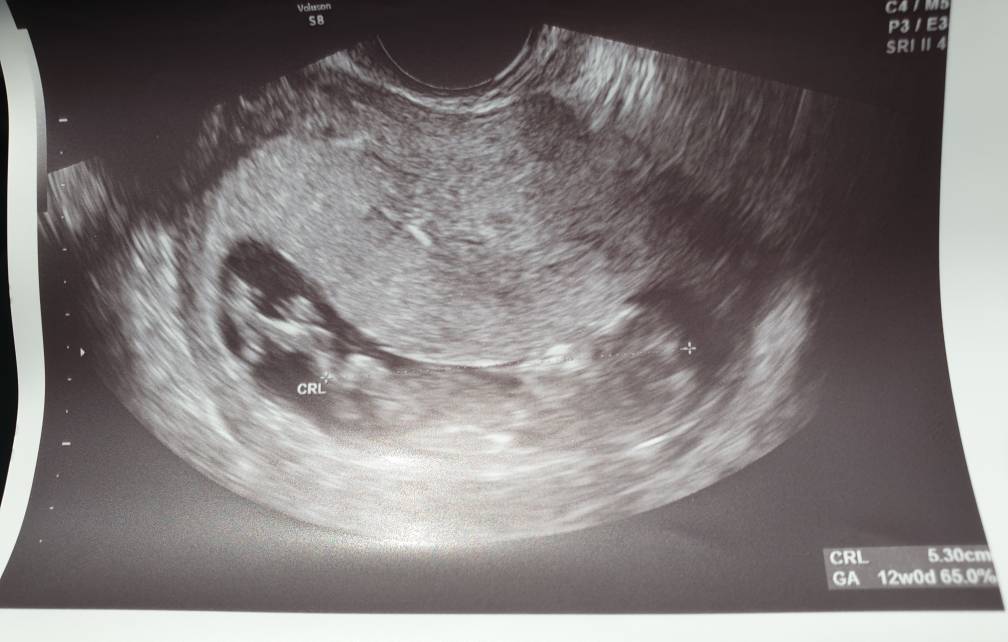

Hej mamuśki! Jestem właśnie po USG genetycznym. Strasznie szybko mi je zrobił, ale sprawdził wszystko po kilka razy i wygląda na to, że wszystko ok! Jedyne czego nie zobaczył to pęcherza, ale powiedział,że pewnie maluch się opróżnił i dlatego nie widać no i nie zbadał dokładnie serduszka, ale biło prawidłowo. Czy, któraś też tak już miała? Zrobiłam też pappa i za tydzień mam odebrać ocenę ryzyka więc nadal nieco stresu jest. Termin mi się z USG przesunął na 30 grudzień ale zostaje z wami!;) Co do obliczania tygodni ciąży - dziś na usg miałam 12t2d i lekarz na zaświadczeniu napisał że to już 13 tydzień -taką wersję wolę;)